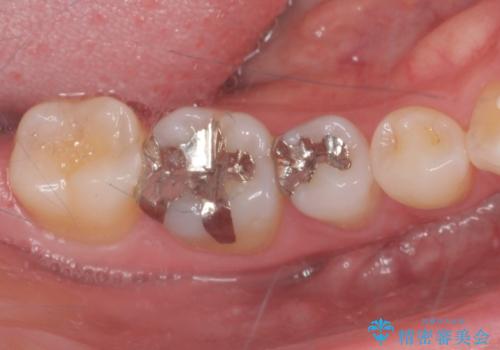

銀の詰め物を白くしたい。

- 銀が目立つのがやだとの事で来院。

二つとも一緒に治療可能だが、まずは一箇所とのご希望だったので

一つずつ治療を行うことにしました。

銀の詰め物を外し、拡大鏡で虫歯がないか確認してe-maxインレーで治療をしました。